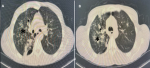

Diagnostic assessment: laboratory tests revealed acute renal failure with a creatinine level of 199 µmol/l and nephrotic syndrome with proteinuria at 11 g/24 hours, albuminemia at 19 g/dl, and proteinemia at 42 g/dl. Renal ultrasound showed two kidneys of normal size with good corticomedullary differentiation. Initially, rifampicin-induced nephrotoxicity was suspected, leading to its discontinuation. Renal function deteriorated rapidly, with levels increasing from 199 µmol/l to 504 µmol/l over 10 days, and hemoglobin decreased to 7.7 g/dl by December 16, 2023. An emergency chest X-ray revealed findings suggestive of pulmonary tuberculosis with signs of activity but no evidence of intra-alveolar hemorrhage (Figure 1). Thoracic computed tomography (CT) showed consolidation with centrilobular branching micronodules, consistent with a tree-in-bud pattern, predominantly affecting the right upper lobe, associated with peribronchovascular thickening (Figure 2). In case of acute nephritic syndrome, we performed autoimmune serologies (ANCA, ANA, anti-GBM antibodies, and complement), which were negative. Serology for hepatitis B and C was negative.

Figure 2: A,B) thoracic computed tomography (CT) of both lungs of the patient; consolidation with centrilobular branching micronodules, consistent with a tree-in-bud pattern, predominantly affecting the right upper lobe (*); peribronchovascular thickening (↓)